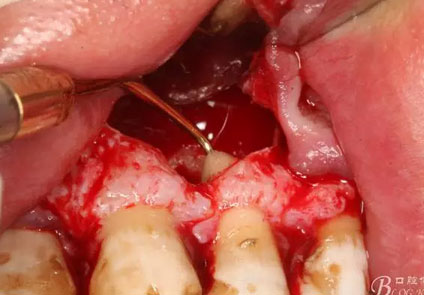

圖17.超聲骨刀根尖切除+倒預(yù)備根管

圖18.MTA倒充填完成根尖區(qū)域